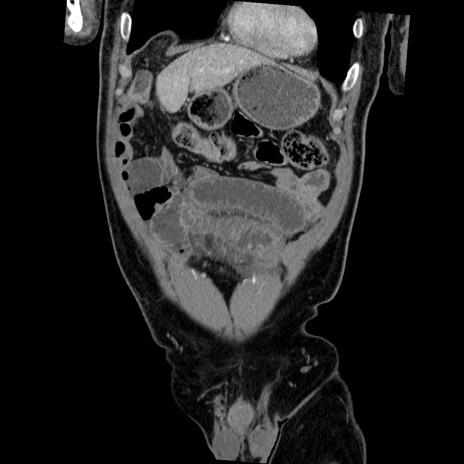

横断像

【症例】50歳代男性

【主訴】腹痛

【現病歴】AVMからの被殻出血のため回復期リハ病棟入院中。 本日午後3時頃急に下腹部痛が出現した。

【既往歴】AVM、被殻出血、虫垂炎、高血圧

【身体所見】意識晴明、左半身不全麻痺、会話の理解は良好、36.5°C、腹部:膨隆、全体に板状硬、下腹部正中に圧痛点あり、反跳痛-、筋性防御不明、右下腹部にope scar

【データ】WBC 9400、CRP 0.06